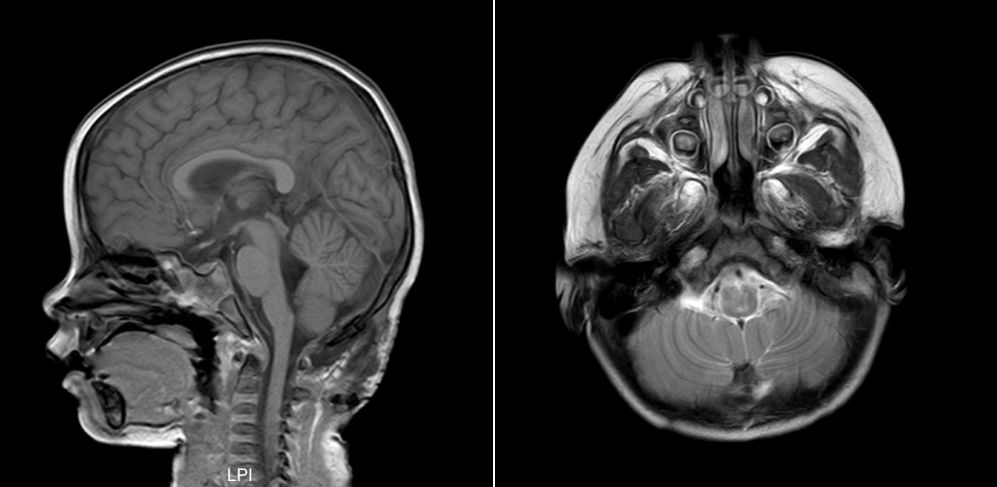

一周后术后复查头颅MRI,未见颅内出血,异物残留征象,未见有颅内脓肿(图6)。